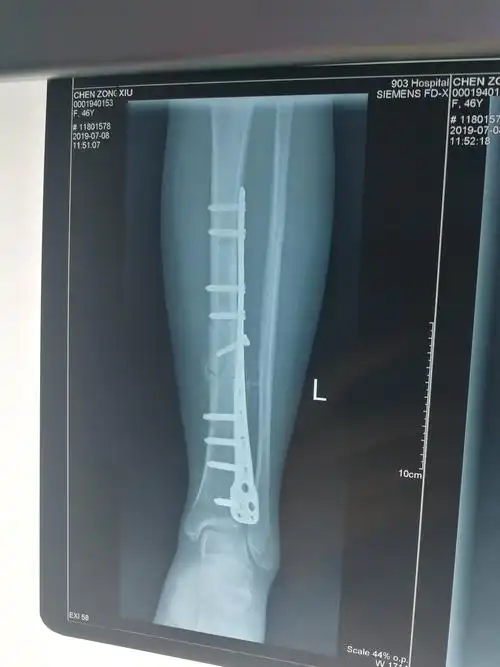

术后三个月,x光片可见骨痂形成,患者恢复良好!家属满意!继续观察!

见左胫骨骨折端为纤维组织填充,无连续性骨痂,无明显的炎性渗出物

经过2个月的治疗后复查片可见骨折端对位对线良好,已有骨痂生成.

经过1个月的治疗后复查片可见骨折端对位对线良好,可见大量骨痂生长.

术后2月骨痂生长良好